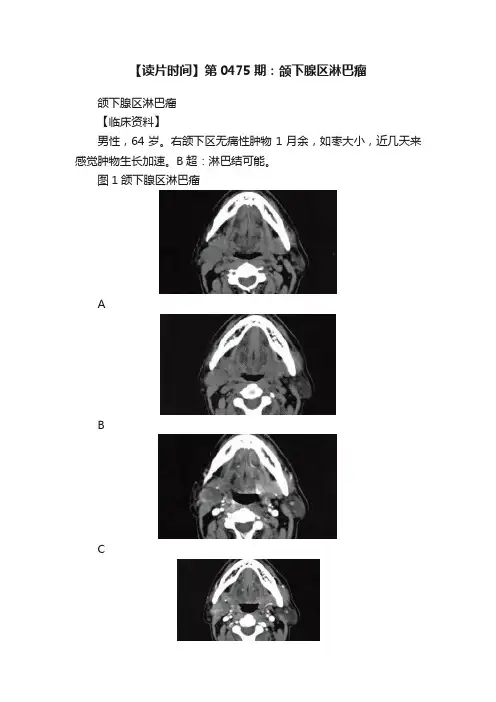

【读片时间】第0475期:颌下腺区淋巴瘤颌下腺区淋巴瘤【临床资料】男性,64岁。

右颌下区无痛性肿物1月余,如枣大小,近几天来感觉肿物生长加速。

B超:淋巴结可能。

图1颌下腺区淋巴瘤ABCDEF【影像学检查】A.B.CT平扫右侧颌下腺后外方见椭圆形软组织肿块影,密度不均匀,其内可见类圆形低密度坏死区,未见明显钙化灶。

病灶边缘光整,与颌下腺之间分界尚清;C?F.增强扫描病灶呈不均匀环形中等程度强化,与周围肌肉强化程度相仿,内侧可见新月形无强化坏死区,冠状位显示更为清晰,颌下腺可见外压性凹陷【最后诊断】淋巴瘤(术后病理)。